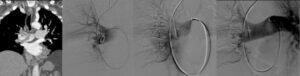

Con approccio dalla vena giugulare interna (collo) o dalla vena femorale comune (inguine),

il Radiologo Interventista porta un catetere dedicato nella sede del trombo in arteria

polmonare. La corretta posizione viene controllata con le radiazioni e mezzo di contrasto.Per i Radiologi Interventisti, le possibilità sono molteplici:

➜ Trombolisi catetere-diretta: iniezione loco-regionale di farmaco fibrinolitico

(che non poteva essere somministrato per via sistemica)➜ Trombectomia meccanica:

- Frammentazione del trombo

- Aspirazione del trombo

- Trombectomia reolitica

- Trattamenti di trombectomia combinati

Efficacia e sicurezza dei trattamenti endovascolari per embolia polmonare

Hanno lo scopo di migliorare nel più breve tempo possibile le funzioni del cuore destro e ridurre

l’ipertensione polmonare acuta che si è instaurata.Si tratta di procedure salva vita.

Devono essere eseguite in centri ad alto volume e da personale altamente specializzato.